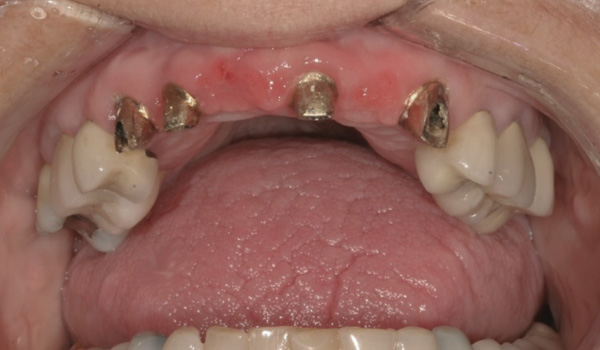

Case 1 – Re-preparing Abutments Intraorally

Background: This patient had a failing maxillary dentition and refused to wear a removable prosthesis. A staged approach was employed to retain some of his natural tooth abutments, and recession was noticed at the time of the impression for the second group of implants. Figure 1 shows the patient following insertion of the first set of implant custom abutments; the adjacent natural teeth are still present to support the provisional bridge. Seven months later, as shown in Figure 2, those first-stage custom abutments exhibited evidence of 1 mm to 3 mm of recession.

Results: A decision was made to re-prepare all of the abutments intraorally (Figure 3) so that all abutment margins would be at or below the gingival margin. (Of note, teeth Nos. 8 and 9, also shown in Figure 3, were later submerged for the case to be fully implant-supported.) While re-preparation greatly improved the esthetics of the final result, it required retraction cord placement, new impressions, and new castings.

Figure 3 Abutments re-prepared intraorally.

Figure 3